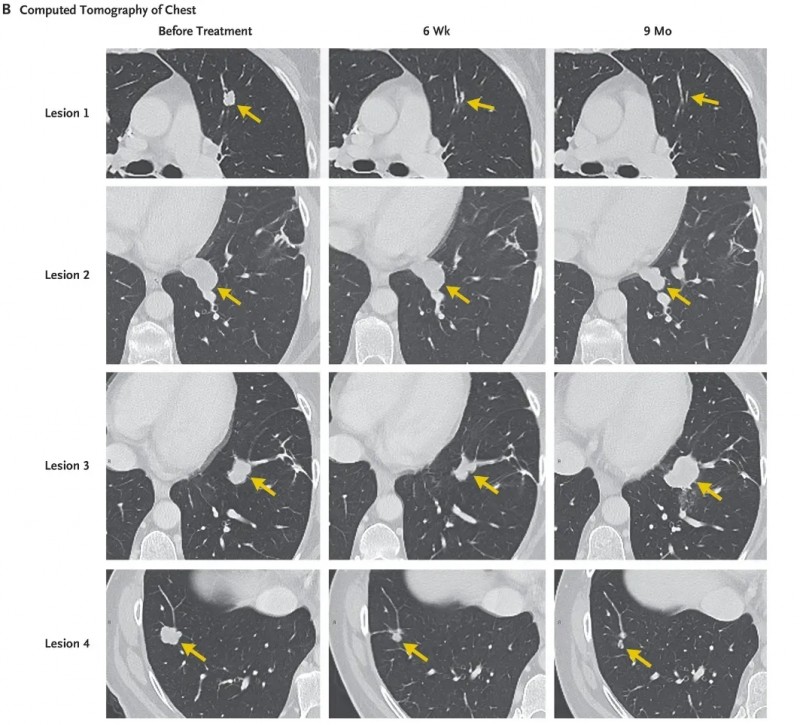

治疗效果远超预期:治疗40天后首次随访,CT检查显示,患者肺部7个转移病灶已全部消退。治疗后9个月复查,其中6个病灶仍维持完全消退或持续消退状态(详见下图),患者在此期间实现了9个月的部分缓解(依据实体瘤疗效评价标准)。仅剩余的病灶3未完全消退且出现进展,患者随后接受胸腔镜(VATS)手术切除该病灶及病灶2,术后正电子发射断层扫描(PET-CT)结果呈阴性,提示无肿瘤活性。

更为惊喜的是,截至目前,病灶切除术后已4个月,患者临床无任何疾病迹象。从确诊时担忧“活不过50岁”的焦虑,到如今顺利度过50岁生日的安心,她正满心期待未来陪伴家人的更多美好时光,TIL细胞治疗无疑为她点亮了生命的新希望!

▲图源“The Philadelphia Inquirer”,版权归原作者所有,如无意中侵犯了知识产权,请联系我们删除